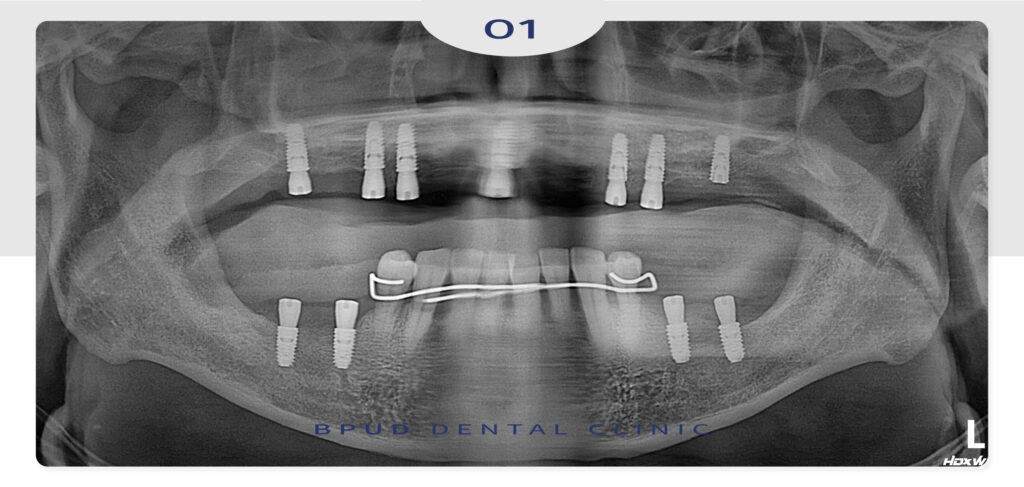

최종 보철물까지 완료한 모습입니다.

틀니보다 편하고 심미적 기능적으로

만족해하셨으며 위 앞니가 많이 튀어나올수도

있는 상황에서 만족스러운 결과를 도출하였습니다.